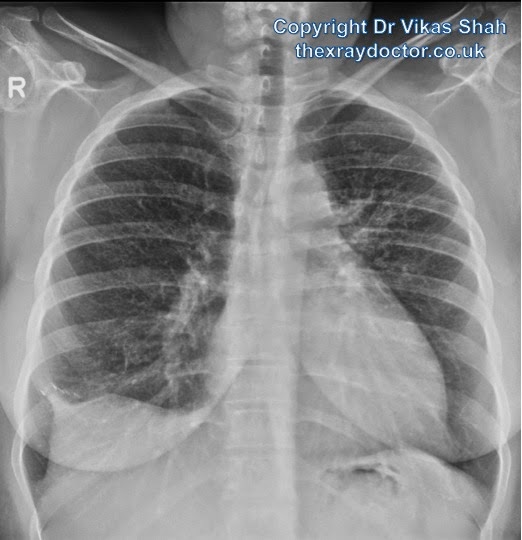

From www.thexraydoctor.co.uk

the xray doctor A young woman with shortness of breath What Does A Chest X-Ray Show For Shortness Of Breath Symptoms may include wheezing, shortness of breath, chest pain, and coughing. It might feel like your chest is tight, you’re gasping for air or you’re working harder to breathe. Dyspnea, or shortness of breath, is the feeling that you can’t get enough air into your lungs. During a pulmonary function test, you blow into a device called a spirometer, which. What Does A Chest X-Ray Show For Shortness Of Breath.